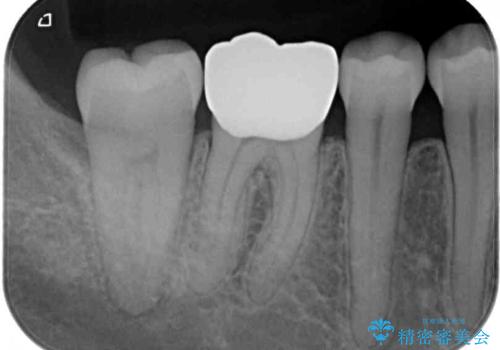

- 人と話す際に、下顎の奥にある銀歯が目立って気になるとのことで来院された患者様です。

左右の奥歯に銀歯のクラウンが装着されていたため、銀歯除去後に仮歯に置き換え、フルジルコニアクラウンにて補綴治療を行うこととしました。

フルジルコニアクラウンは、やや光沢のある材質ですが、奥歯に装着した場合にはさほど気にならず、自然な口元の印象となりました。